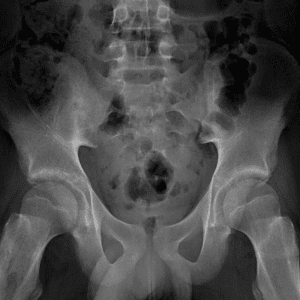

Pediatric Radiographs